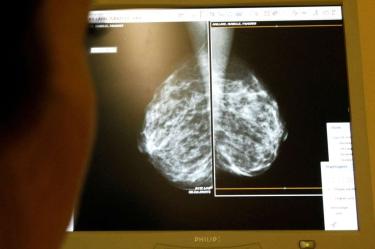

FDA aprueba nuevo tratamiento contra el cáncer de mama en etapas tempranas

La Administración de Alimentos y Medicamentos de Estados Unidos (FDA) otorgó el martes la aprobación al uso de ribociclib adyuvante (Kisqali) en combinación con un inhibidor de la aromatasa, destinado a pacientes adultas con cáncer de mama en etapa temprana, específicamente en los estados II y III. Este tratamiento está indicado para aquellos con receptor hormonal positivo (HR) y HER2 negativo, que presentan un alto riesgo de recurrencia.